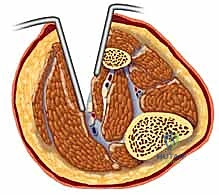

الخطوة الثانية: الشق الخارجي (الجانبي - Anterolateral Incision)

يهدف هذا الشق إلى تحرير الحيز الأمامي والحيز الجانبي.

* يتم عمل شق طولي طويل جدًا (حوالي 15-20 سم) على الجانب الخارجي للساق، يبدأ من أسفل الركبة ويمتد نحو الكاحل.

* يتم شق اللفافة العميقة للحيز الأمامي أولاً، مع الحذر الشديد لتجنب إصابة العصب الشظوي السطحي (Superficial Peroneal Nerve).

* ثم يتم توجيه المشرط لشق اللفافة الخاصة بالحيز الجانبي. بمجرد فتح اللفافة، تبرز العضلات المحتقنة للخارج بشكل ملحوظ، مما يدل على تحرير الضغط.

الخطوة الثالثة: الشق الداخلي (الإنسي - Posteromedial Incision)

يهدف هذا الشق إلى تحرير الحيز الخلفي السطحي والحيز الخلفي العميق (وهو الأهم).

* يتم عمل شق طولي ثانٍ على الجانب الداخلي للساق، خلف حافة عظمة الزند (Tibia) بحوالي 2 سم، لتجنب الوريد الصافن الكبير (Saphenous Vein) والعصب المرافق له.

* يتم شق لفافة الحيز الخلفي السطحي (عضلات السمانة).

* بعد ذلك، يقوم الجراح بسحب عضلات السمانة للخلف للوصول إلى اللفافة العميقة جداً التي تغطي الحيز الخلفي العميق. يتم شقها بعناية فائقة لتحرير العضلات العميقة والشرايين الحيوية المجاورة.